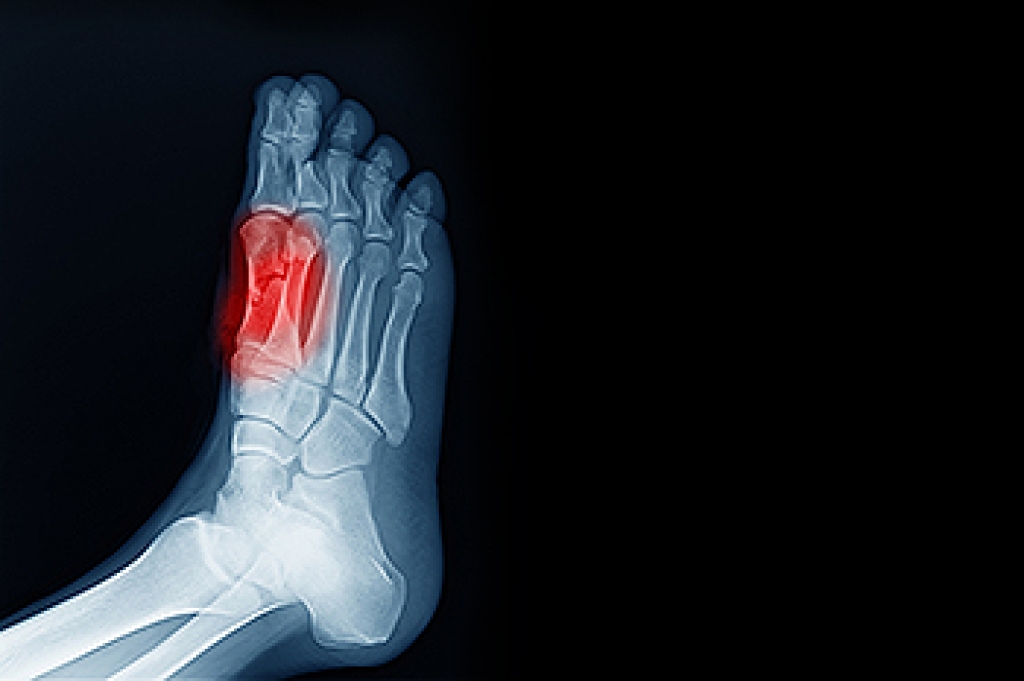

Sesamoiditis is a condition of the foot that affects the ball of the foot. It is more common in younger people than it is in older people. It can also occur with people who have begun a new exercise program, since their bodies are adjusting to the new physical regimen. Pain may also be caused by the inflammation of tendons surrounding the bones. It is important to seek treatment in its early stages because if you ignore the pain, this condition can lead to more serious problems such as severe irritation and bone fractures.